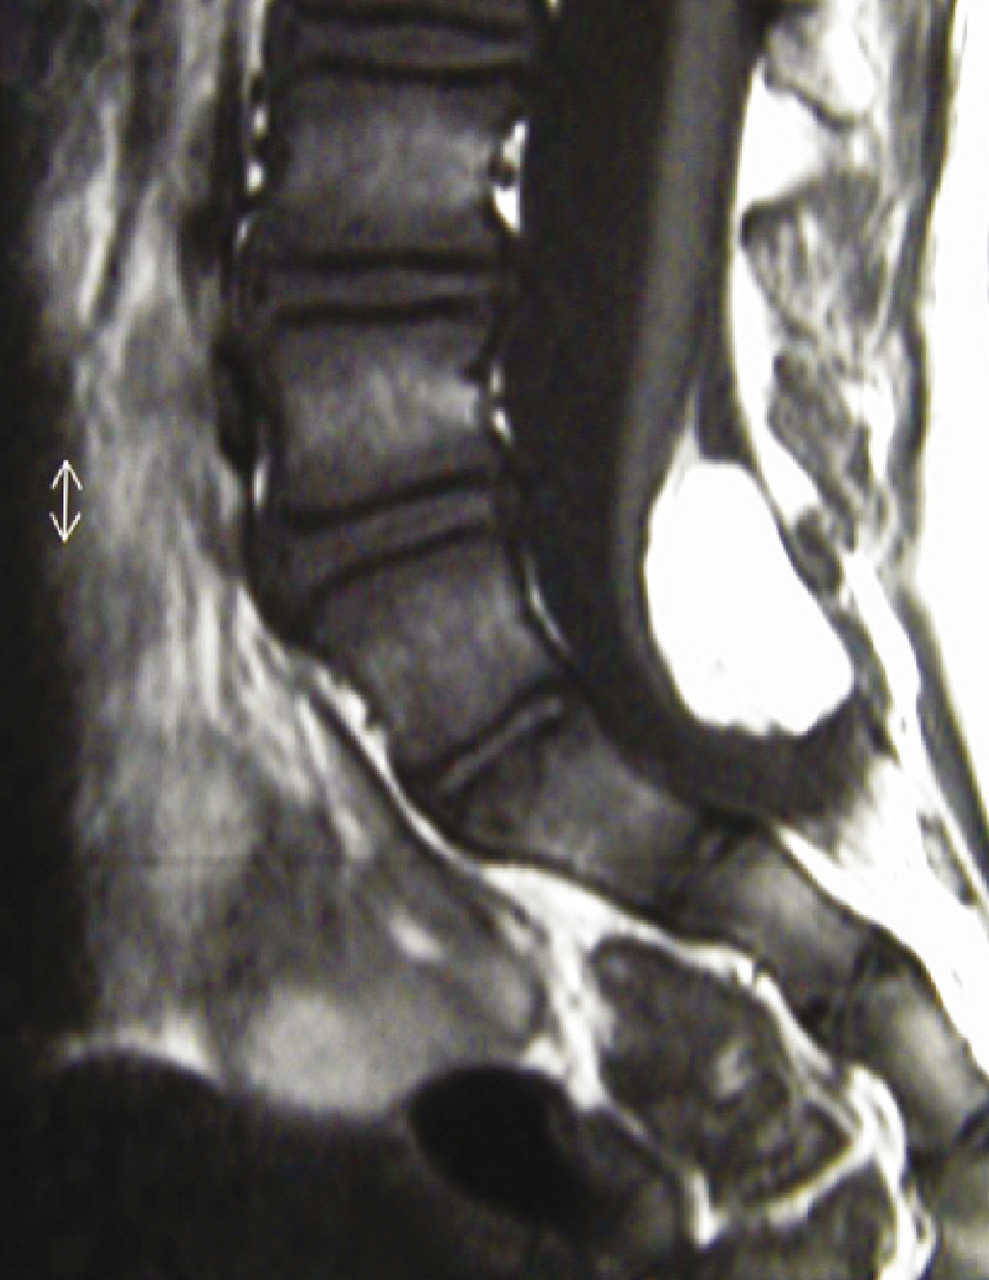

Les malformations vertébro-médullaires ou dysraphismes sont la cause la plus fréquente de troubles mictionnels neurologiques de l’enfant. Ces dysraphismes sont suspectés par un stigmate cutané sur le raphé médian lombaire souvent typique (fossette, masse sous-cutanée [fig. 4], appendice caudal, angiome plan ou tubéreux...). Les dysraphismes fermés (lipome du cône médullaire [fig. 5], lipome du filum terminal, syndrome de régression caudale...) sont des atteintes caudales sans aucune anomalie cérébrale ni cervico-occipitale contrairement aux dysraphismes ouverts (myéloméningocèles). Ces dysraphismes fermés sont responsables de troubles neurologiques médullaires essentiellement sphinctériens et distaux des membres inférieurs (pieds creux varus équin, inégalité de longueur des membres inférieurs). De ce fait, l’examen de tout enfant porteur de troubles urinaires doit comporter un examen clinique de la partie médiane du rachis lombo-sacré et des pieds.